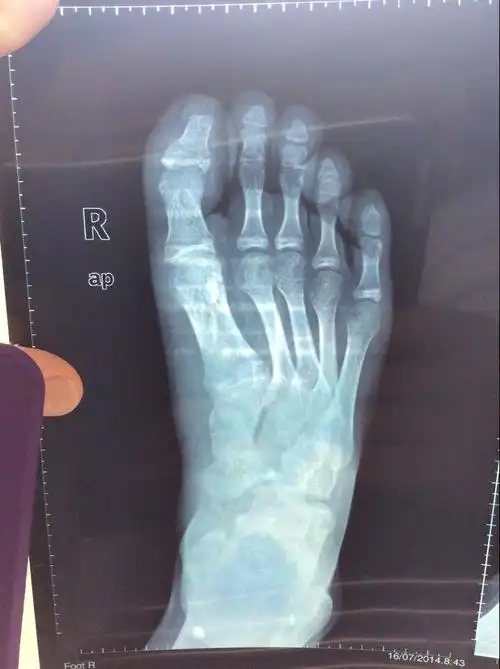

右脚大拇指基底骨折,现在9周了,能不能拆石膏正常走路?我15岁